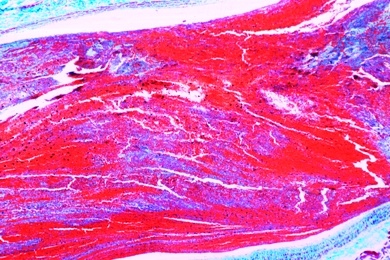

Mikropräparate in Serie - Pathologische Histologie des Menschen, Basisserie, 50 Präparate mit Begleittext

Pathologische Histologie des Menschen, Basisserie 50 Präparate mit ausführlichem Begleittext,

Unsere Mikropräparate werden unter wissenschaftlicher Leitung hergestellt. Sachgemäß fixiertes und konserviertes Ausgangsmaterial ist die Voraussetzung für einwandfreie Präparate. Wir verwenden deshalb auf diese Arbeitsgänge besondere Sorgfalt. Die Herstellung der Mikrotomschnitte erfolgt durch erfahrene Fachkräfte, Schneidetechnik und Schnittdicke werden den Objekten angepaßt. Aus der großen Zahl der in der Mikroskopie üblichen Färbemethoden wählen wir solche, die eine klare und kontrastreiche Darstellung der gewünschten Strukturen mit bester Haltbarkeit verbinden. Meist handelt es sich dabei um Mehrfachfärbungen.